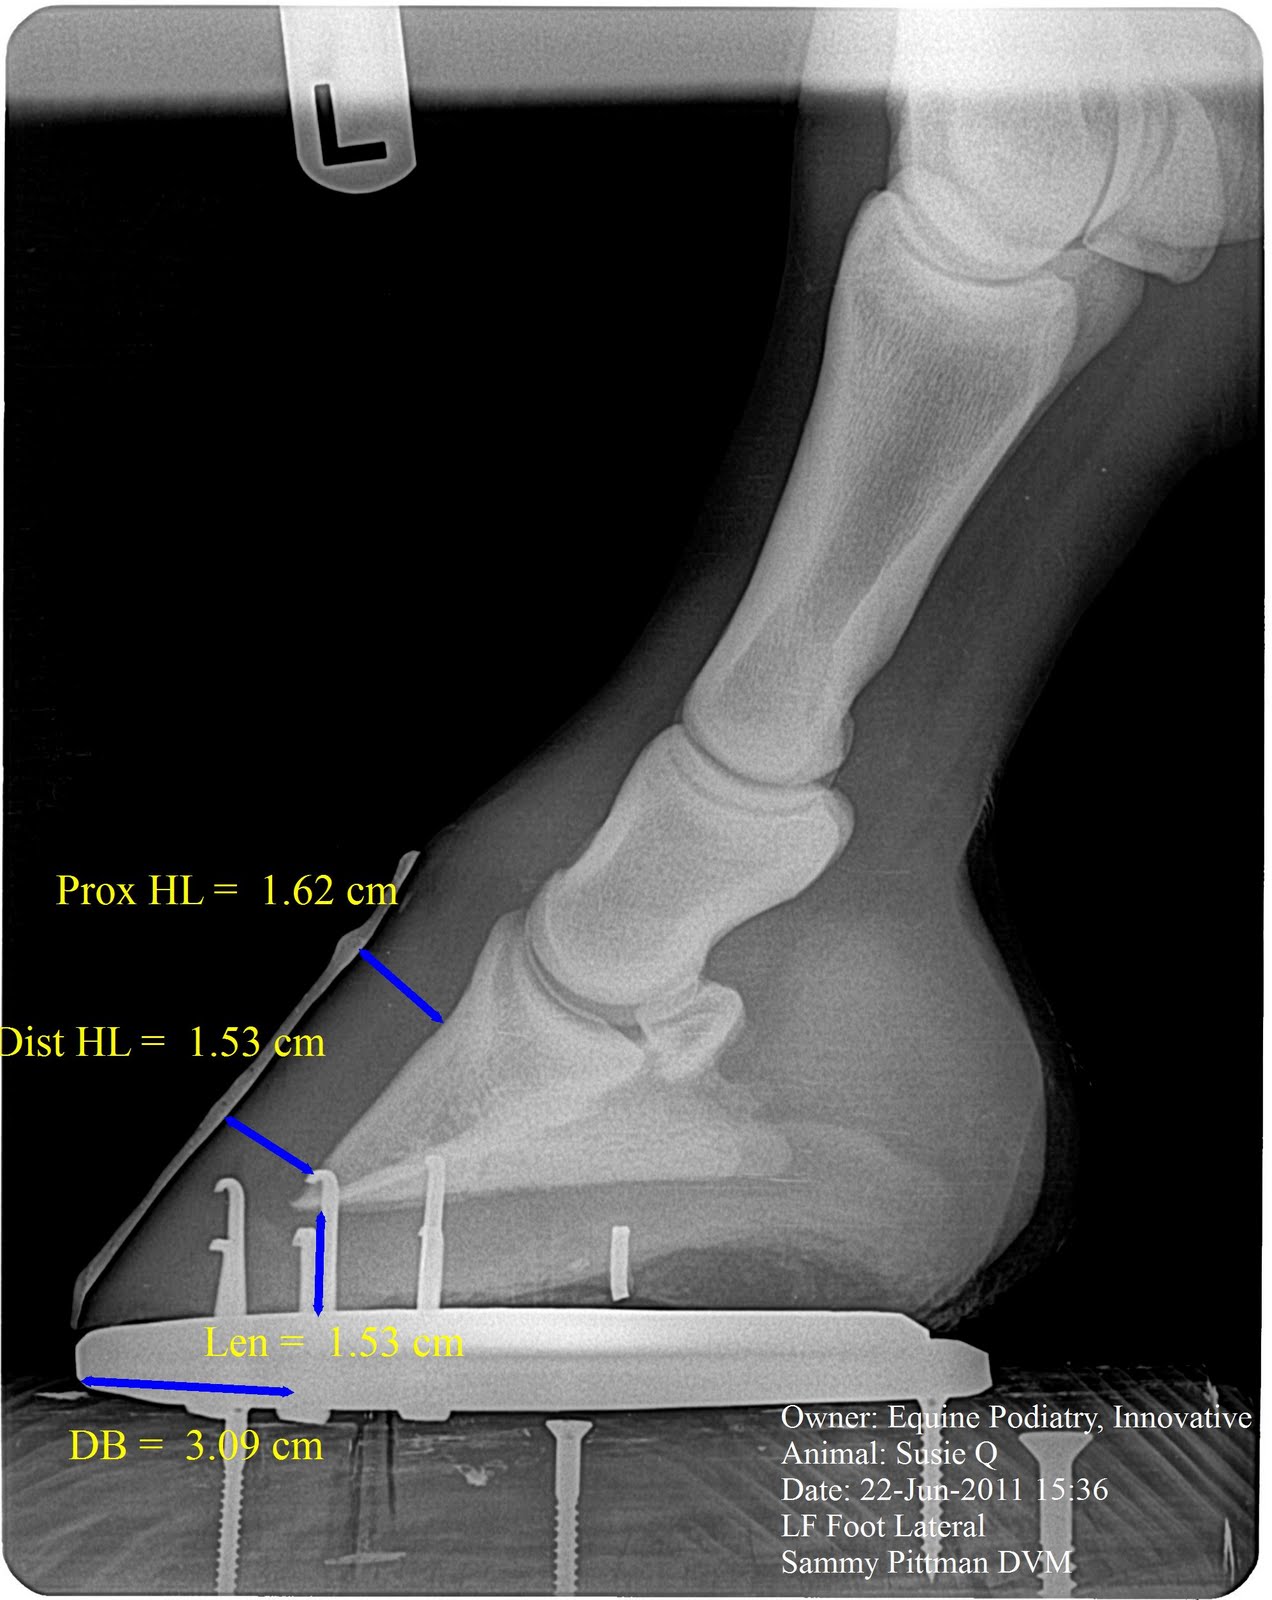

| Here is a shot after venogram and I placed her in a more common flat steel shoe in a manner in which I would have placed prior to a changing of my mind of how forces interact in the foot. The DB (digital breakover) is 30 mm. This will continue to lengthen over time and reaching a likely 40-45mm by the next shoeing cycle, possibly. I also surmise that a gradual reduction in sole depth will also occur due to the long and every increasing DB and increasing forces from ddf on solar corium and dorsal hoof decreasing the circulation. |

| lateral view of flat steel shoe. For those of you who know me, know that this was very difficult for me to do. HEHEHEHEHEHe |